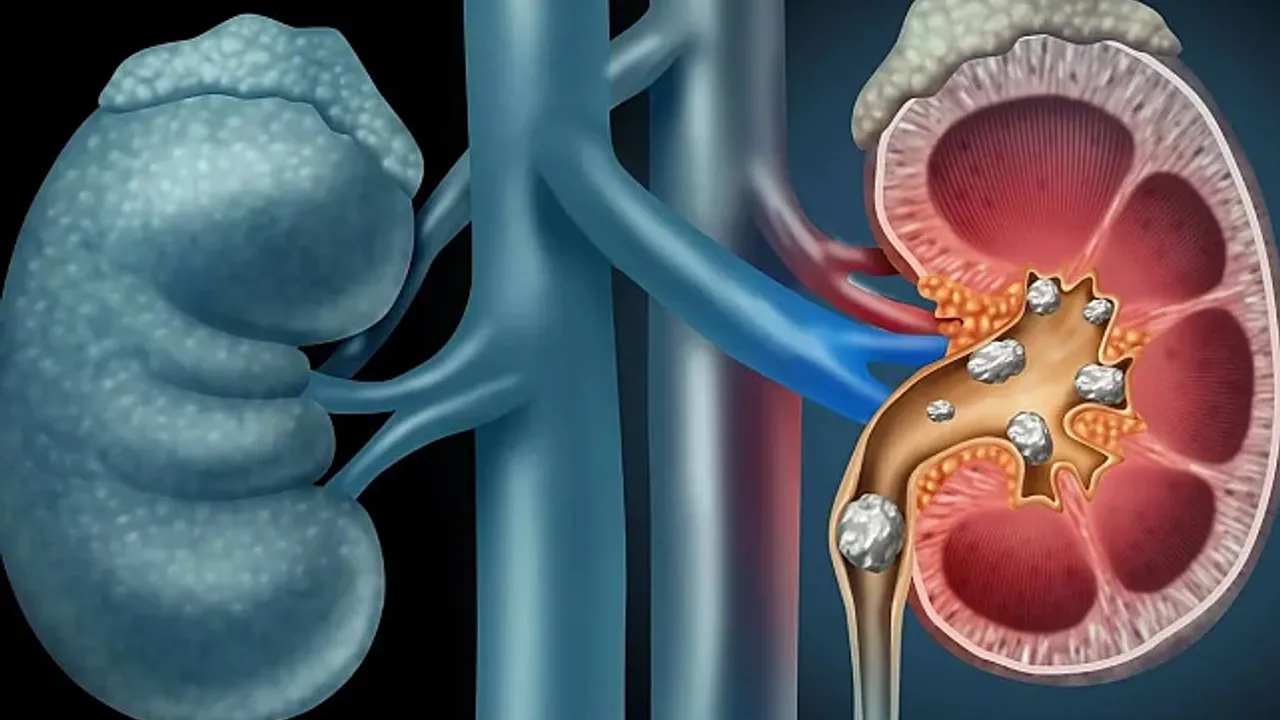

Vücuda alınan sağlıksız, sindirimi ve emilimi zor gıdalar böbrekler tarafından süzülemediğinde bulunduğu yere yapışıp kalabiliyor. Bu da bir dizi böbrek rahatsızlığına yol açıyor. Uzmanlar, dengeli ve sağlıklı beslenmenin böbrek taşı oluşumunu engellediğini savundu.